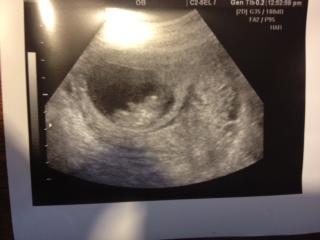

Attachment 5398Can you guess based on ramzi, nub or skull? 10 week abdominal scan. I have had lots of loss so just happy she/he looks healthy.

no idea sorry hunny - pic is far too small to see a nub and babe a bit too little to make it that accurate anyway if you could, nubs are best done at 12-13 weeks

from what i know of ramzi's method its all about which side the placenta implants on and to be accurate you need to ask the tech when they scan you as different methods of scanning provide different angled pictures and affect the results (i think its to do with whether image is a reversed reflection or viewed horizontally) don't really get the specifics but its not the easiest things to do unless you know what your doing - and i don't but didn't want to not answer either when you had no replies x

Thank you for replying! The tech said "right" but she did not know what I was talking about. I hope she was referring to something else besides the placenta.

Too early to tell, but congrats on the healthy bean.